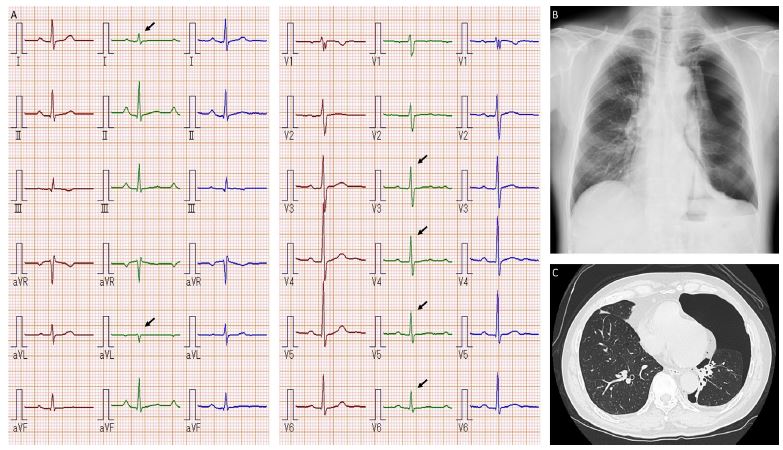

A 78-year-old man presented with intermittent chest discomfort. He had a history of surgery for colon cancer and hypertension and was taking amlodipine 5 mg daily and valsartan 80 mg daily. On presentation, his vital signs and physical examination were normal. Electrocardiography (ECG) was normal (Figure 1A, brown), and echocardiography showed normal chamber sizes and left ventricular function. The patient was scheduled for Holter monitoring and exercise 201-thallium scintigraphy. On the day of the scintigraphy, he reported developing dyspnea on exertion several days earlier, prior to the start of exercise. ECG showed no ST-T segment changes (Figure 1A, green), although it was later confirmed that the R-wave height had decreased, especially in the anterolateral leads (Figure 1A, arrows).

Exercise scintigraphy was canceled, as neither unstable angina nor heart failure could be completely ruled out. The patient was transferred to the outpatient cardiology department. The jugular venous pressure was not elevated, and no abnormalities were observed on cardiac auscultation. However, respiratory sounds were diminished, and there was decreased tactile fremitus on the left side. Chest radiography demonstrated a left-sided pneumothorax (B), and computed tomography (C) revealed total collapse of the upper lobe and partial collapse of the lower lobe. Notably, air retention in the left lung cavity coincided with the leads in which the QRS amplitudes were decreased after the pneumothorax. A chest tube was placed in the left chest cavity, and the ECG returned to previous findings (Figure 1A, blue). A diagnosis of paroxysmal atrial fibrillation was later made based on Holter monitoring for his initial symptoms.

In the present patient, the main ECG changes after pneumothorax were associated with QRS amplitude. In an ECG analysis of 40 consecutive patients with spontaneous pneumothorax by Krenke and colleagues [3], QRS amplitude in leads V2 to V6 was significantly decreased in patients with left-sided pneumothorax, while right-sided pneumothorax was associated with an increase in QRS amplitude in leads V5 and V6. The underlying mechanism remains to be elucidated, but it is intuitive to consider that QRS amplitude alterations may be attributed to the displacement of the heart within the thoracic cavity due to pneumothorax [1,4]. Given the distributions of decreased QRS amplitudes and air retention after pneumothorax in the present patient, heart displacement is the most likely cause of his ECG changes. This speculation is further supported by the fact that the ECG changes returned to previous findings after treatment for pneumothorax and that echocardiography performed before the pneumothorax was unremarkable.

Figure 1: Clinical image.